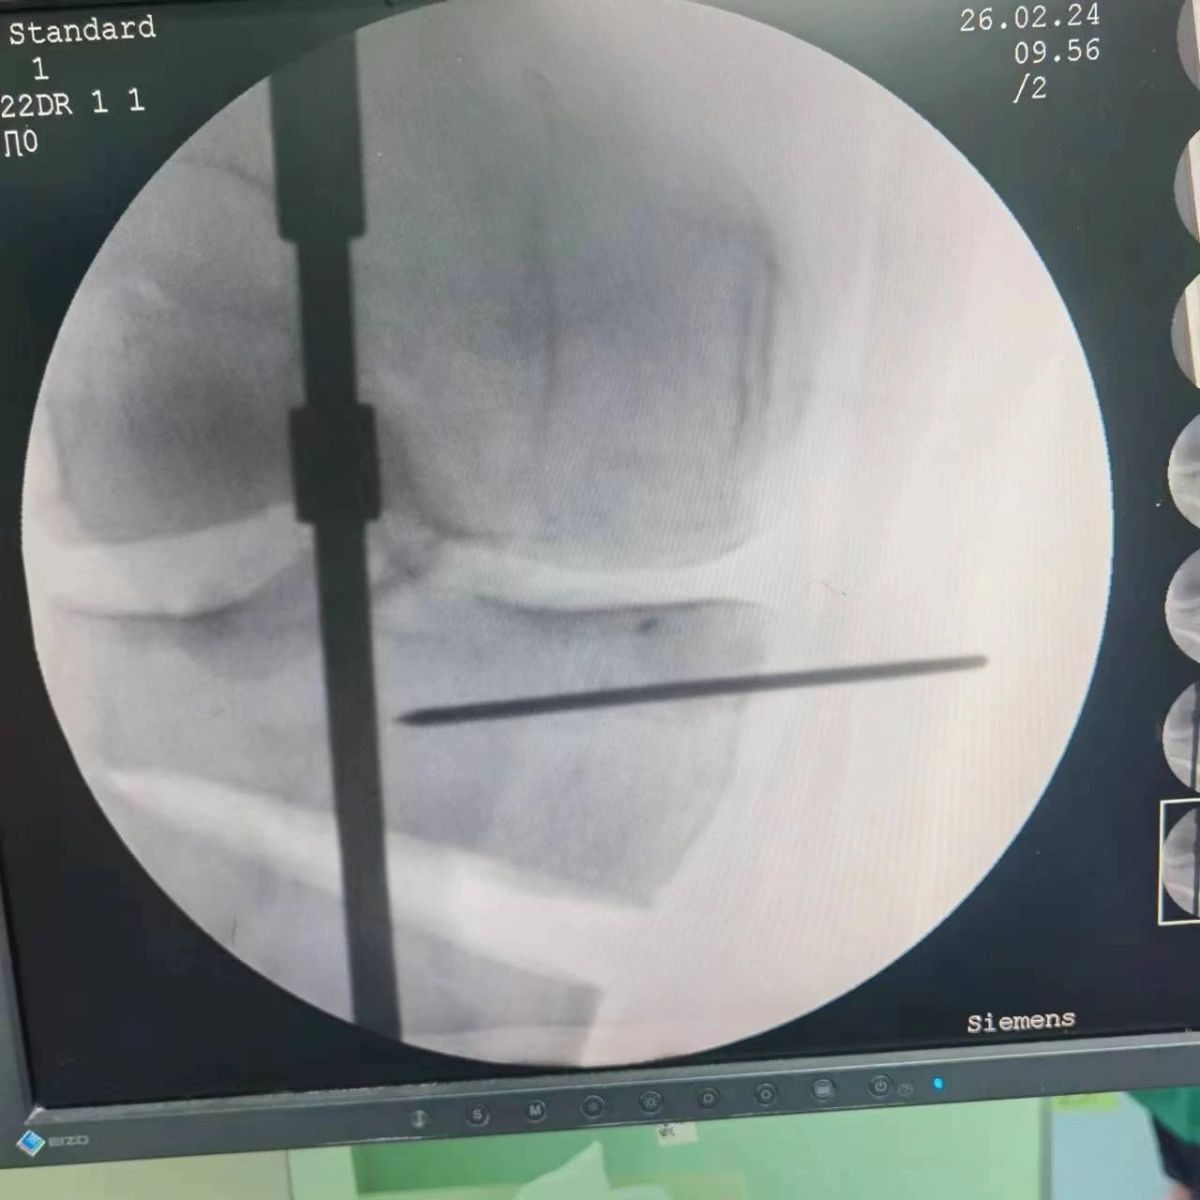

2月26日,漯河市骨科醫院(漯河醫專二附院、漯河市立醫院)膝關節外科、運動損傷科(骨六科)在保膝治療方面取得了新的突破,李付彬主任帶領岳龍等團隊醫師,順利完成“計算機精準術前規劃聯合3D打印截骨導板輔助脛骨高位截骨治療膝關節骨性關節炎”的手術,這在漯河市尚屬首例!

患者為一名45歲男性,查體及X片可見明顯的膝內翻,內翻畸形主要來源于脛骨近端,關節鏡下可見內側間室軟骨全層磨損,疼痛較重,年紀輕輕幾乎喪失工作能力。對于這種日常活動需求比較大的患者朋友,我們盡最大可能給予保膝治療,李付彬主任給患者詳細講解了保膝治療的方案(脛骨近端高位截骨)及預期效果,給患者帶來了極大希望。為了更精確、更微創的治療,李付彬主任團隊緊跟國內外科技前沿,采用計算機精準術前規劃,并設計3D打印截骨導板,力求給患者帶來更精準、更安全的手術效果。

李付彬主任團隊通過精準術前規劃,設計目標力線及調整撐開角度,轉化成需要撐開的高度,最終設計出同等高度的填充塊,術中驗證力線調整與術前規劃完全一致!

鋼板位置、螺釘位置及長度均可通過術前規劃計算,術中通過定位操作,基本與術前規劃一致,手術快速高效完成,外側合頁保留完整。無任何并發癥出現。術后見鋼板位置及力線糾正近乎完美!

OWHTO手術效果依賴于多個數據參數,比如:截骨的入點、合頁位置的選擇、截骨線的深度、截骨線的方向、撐開的距離等,依托計算機術前精準規劃和3D打印導板可輔助醫生精準控制上述參數,使截骨更準確,真正達到精確的力線調整,減少術中透視次數,縮短手術時間并降低手術風險,從而使得OWHTO得到更好的應用,造福患者。